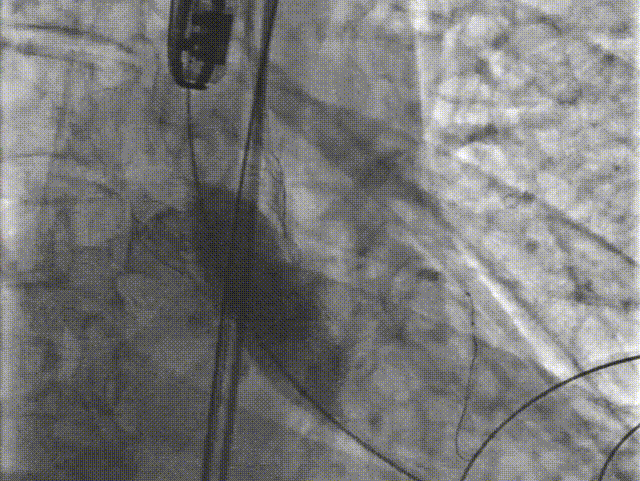

C. 应用交界贴合技术调整人工瓣膜,标准位释放瓣膜并行释放后造影

D. 瓣膜释放后造影显示瓣膜位置良好

E.后扩张

F. 最终造影显示瓣膜位置良好冠脉开口血流正常,撤出冠脉保护